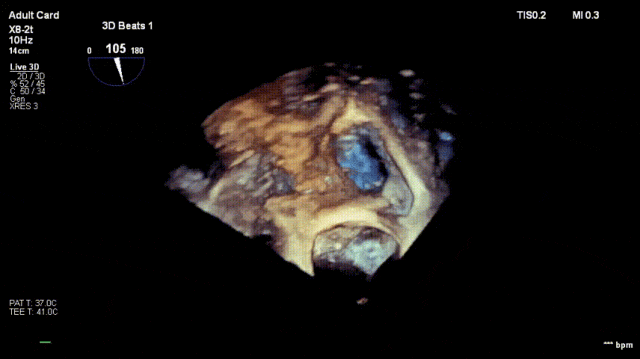

1. Preoperative baseline regurgitation

Regurgitation assessment: Regurgitation severity reduced from preoperative 5+ to 1+.

Annuloplasty effect: The tricuspid annulus area decreased from 13 cm² preoperatively to 7 cm².